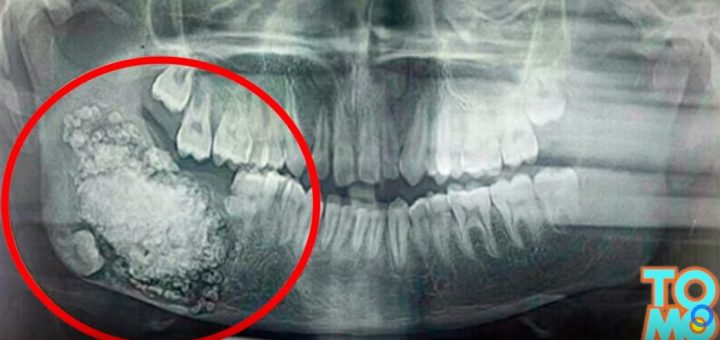

The Tooth Blog